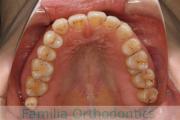

上顎

下顎